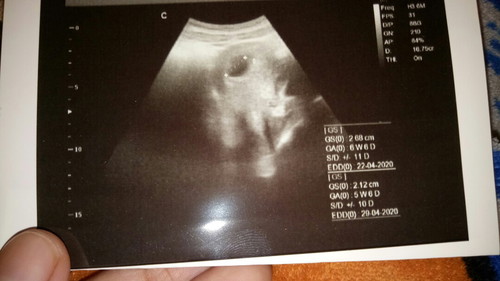

usg 6week

udh telat haid 2 minggu , tadi udah ke dokter kandungan d USG baru keliatan kantongnya disuruh balik lagi 1 bulan lagi kata dokternya usia kandungannya baru 6week , tapi pas saya liat di hasil foto usg.nya ad 2 tulisan yang atas usia 6W6D yang bawah 5W6D itu maksudnya apa ya bun?